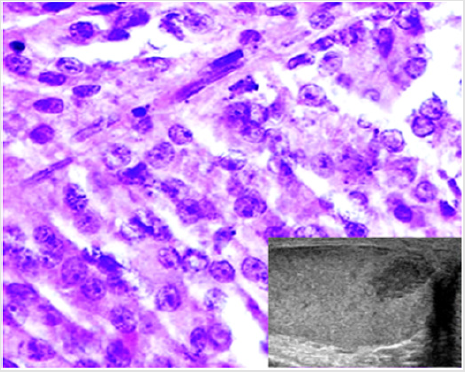

Figure 2: A case of Leydig cell tumor. Histological examination showing cells with abundant slightly eosinophilic cytoplasm, round nuclei and evident nucleoli (H&E, 40x). The neoplasm appeared as a hypoechoic nodule at US scan (inset).